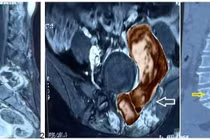

Do cấu trúc mạch máu vùng bụng phức tạp, hình ảnh CT-Scan cho thấy khối u đã che khuất tĩnh mạch chủ dưới – tĩnh mạch lớn nhất của ổ bụng cùng cuống mạch máu thận. Ê-kíp phẫu thuật phải tiến hành bóc tách cẩn thận để bảo tồn các mạch máu quan trọng, tránh gây tổn thương trong quá trình mổ.

u-quai1.png

Ê-kíp bác sĩ phẫu thuật loại bỏ u quái buồng trứng chứa tóc, răng và xương - Ảnh BVCC